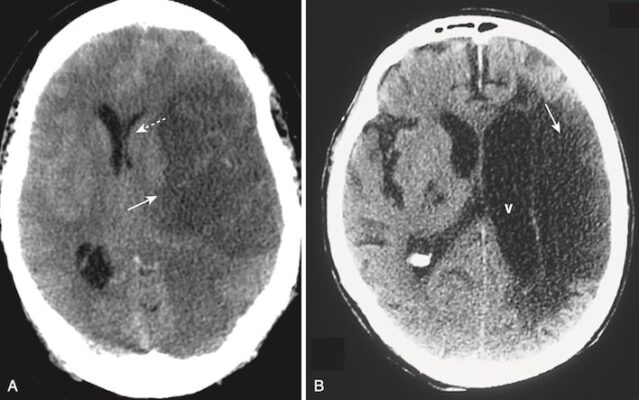

A, Vào khoảng 24 giờ, tổn thương có viền bao quanh tương đối rõ (mũi tên màu trắng đặc) với hiệu ứng choán chỗ biểu hiện bằng sự đẩy lệch của não thất (mũi tên màu trắng chấm), đạt đỉnh điểm từ 3 đến 5 ngày và biến mất sau khoảng 2 đến 4 tuần.

B, Khi đột quỵ trưởng thành, nó mất hiệu ứng choán chỗ, có xu hướng trở thành một tổn thương giảm tín hiệu bờ thậm chí còn rõ nét hơn (mũi tên màu trắng đặc), và có thể kết hợp với giãn não thất kế cận (V) do mất chất não trong vùng bị nhồi máu.